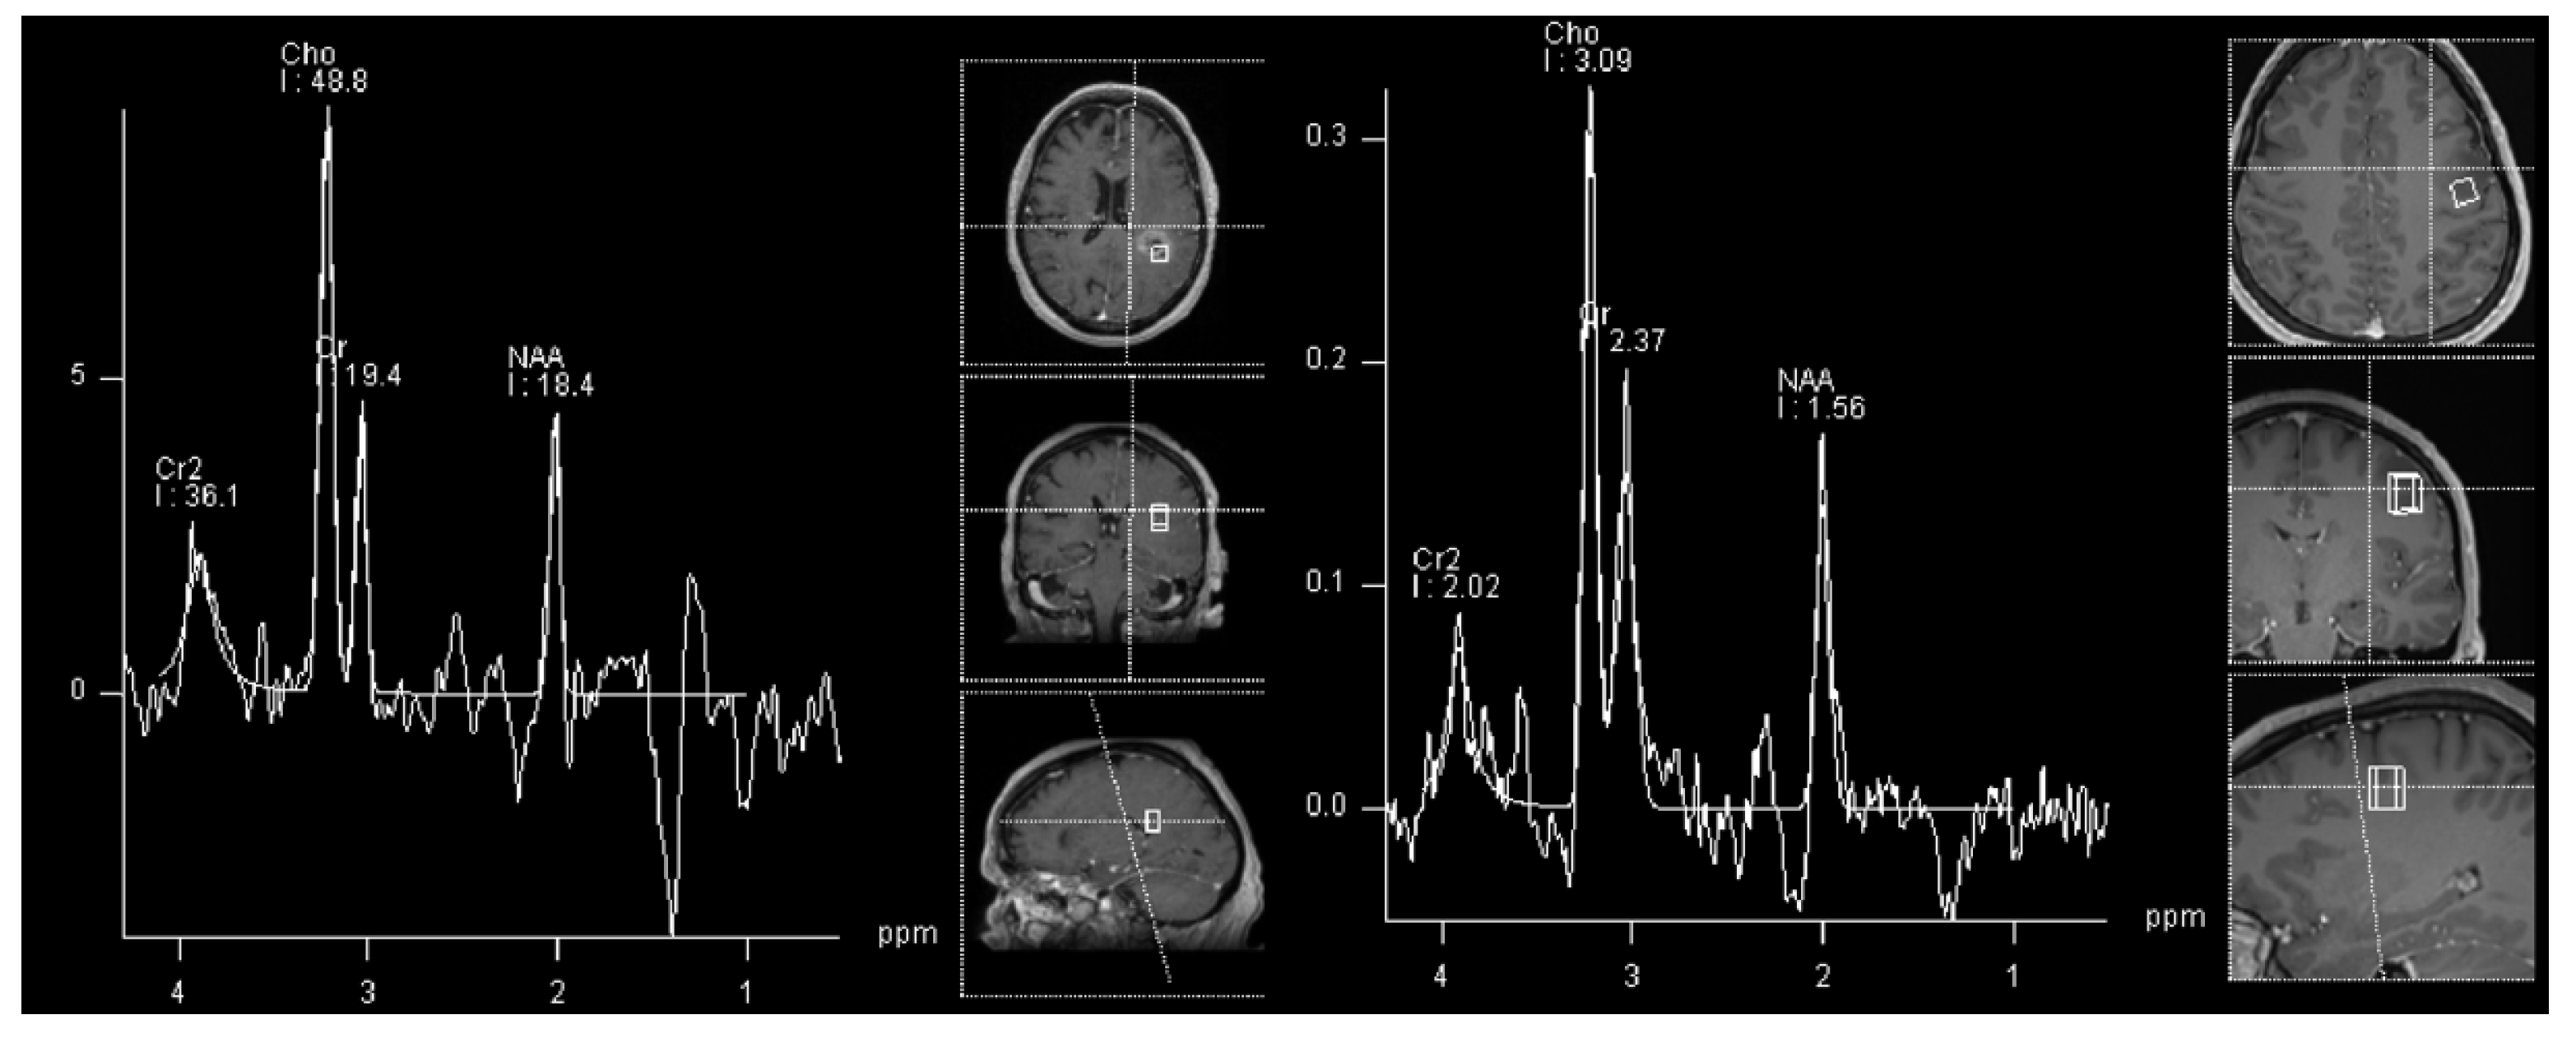

In gliomas, the general rule is that the NAA and Cr decrease, and other metabolites increase with higher tumor grades. Some authors suggest using a Cho/NAA ratio greater than 2.2 to predict higher grade, and a presence of myoinositol to predict the lower grade lesions [41,42]. However, as shown in Figure 3 and in our own experience, low-grade gliomas can also have similar spectra as high-grades (but rarely vice-versa).

Consequently, the most important metabolite in differentiating TP from radiation-induced PsP is choline, as disturbances in the biosynthesis of cell membranes and metabolic turnover are reflected by an increase in choline. As in a primary tumor, choline will be increased in TP, whereas it will be decreased in RN and radiation induced PsP, together with NAA and creatine. In our experience, the most common clinical encounter is with patients that have imaging characteristics of both TP and radiation-induced PsP (Figure 4).

For differentiating between PsP and TP, the following MRS ratios and cut-offs were suggested: a Cho/NAA ratio under 1.47–2.11 and Cho/Cr ration under 0.82–2.25 indicated PsP. Cho/NAA ratio had a mean of 2.72 for TP, and 1.46 for RN (p < 0.01) [61]. Figure 4 shows the Cho/NAA ratio under cut-off for histologically confirmed GBM progression.

Figure 3. Similar 1H-MRS spectra can be appreciated in an adult patient with glioblastoma (left, black arrow) and in a patient with astrocytoma WHO grade 2 (right, white arrowhead) with increased NAA and decreased Cr and Cho.

Figure 4. 1H-MRS in an adult patient with glioblastoma progression (left, black arrow) and in a patient with signs of both progression and radiation necrosis (right, white arrowhead). Cho/NAA ratio is under proposed cut-off for TP in progressive GBM.